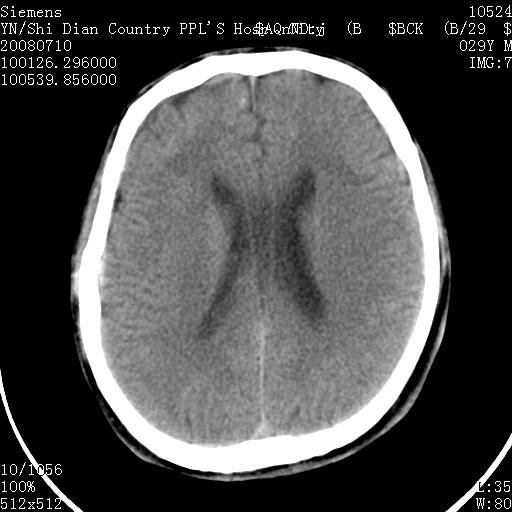

以下是引用pujunzhi在2008-7-10 13:06:00的发言:[br]透明间隔腔

以下是引用随光逐影在2008-7-10 15:19:00的发言:[br]1)考虑左侧尾状核钙化。2)透间隔间腔与vergae腔并存。

以下是引用卜一在2008-7-10 16:43:00的发言:[br]1)考虑左侧尾状核钙化。2)透间隔间腔形成。支持!